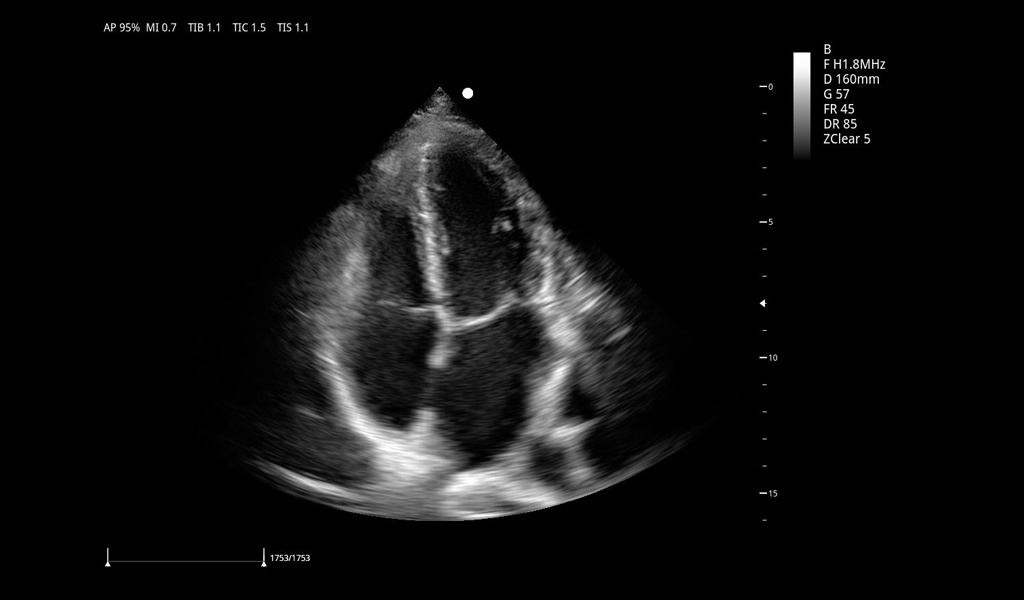

Excelentes imágenes clínicas

|

|

|

|

|

|